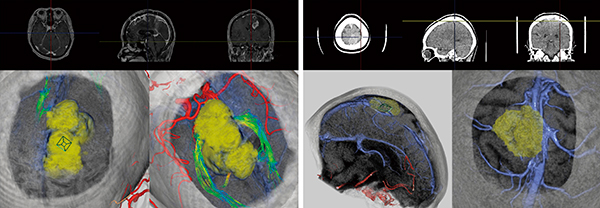

臓器抽出後,シミュレーションステージに移動することで,実際の手術の流れに即した皮膚・骨領域の切開シミュレーションが可能である(図3)。画面は全体像を把握する俯瞰ビューアと,局所的な観察を行う術野ビューアで構成され,俯瞰ビューアでカメラを設置後,局所的に拡大された画像を術野ビューアで観察しながら,皮膚,骨の順に切開し,脳表へのアプローチをシミュレーションする。表示された脳表を視線方向にクリップ(非表示)することで,脳実質内部の血管,神経,腫瘍の観察を行い,腫瘍近傍の血管の走行などを確認するモードも搭載している。

図3 シミュレーションステージでの表示例

グリオーマ症例。骨切離後,脳表をクリップすることで,内部をあらゆる角度から観察できる。それぞれの臓器の透過度は自由に変更できる。